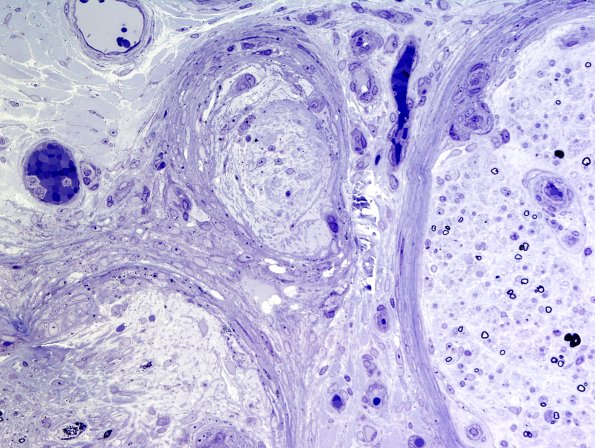

3B4 Sarcoid (Case 3) Plastic 14

An area of perineurial inflammation is seen at several magnifications. (Plastic sections)